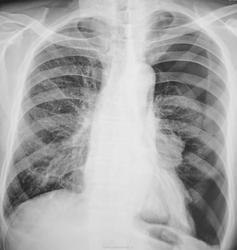

А, вот динамика "от сегодня".

Чего-то за 10 дней так и не расправилось. А дренажной трубки не видно, какое лечение проводится? В синусе выпот и междолевой похоже

Да, динамика не "фонтан", ставили дренаж по Белау.

Но, посчитали, что все хорошо, посчитали без контрольной рентгенограммы...

Междолевого нет - это лёгкое так сдулось  (опустилось-изогнулось)...enlightened

Насчет пневмоторакса понятно , но процесс углубился , через 10 дней картина стала еще ярче с обеих сторон , пневматизация на минимуме, и слева косто-диафрагмальный синус не дифференцируется . При всем уважении ко всем , опять же я новичок и поэтому могу ошибаться ..., к сожаленью

1. Поверьте, не поучаю, просто высказываю свое мнение, посколько принимал уже участие в обсуждении ранее)))

2. Сказать что усугубилась картина, нет, не могу. Все таки, какая никакая ПОЛОЖИТЕЛЬНАЯ динамика в плане расправления левого легкого есть. Да - неполное пока, но что поделать, тому есть обьяснение - раннее удаление дренажа без предшествующего рентгенконтроля, на что было и указано Валентином Львовичем. Теперь придется доводить все консервативно, если не дренировать повторно, а не это, зачастую, уходит МНОГО БОЛЬШЕ времени.

3. Вот примерно так. Говорить о пневмонии, на фоне спавшегося или частично спавшегося легкого, как бы Вам сказать....несколько опрометчиво...ибо легко можно ошибиться...ведь коллабирование легкое БОЛЕЕ интенсивную тень дает....

4. Да - выпот как бы есть, но опять же - ему есть обьяснение - а именно - тот же пневмоторакс, жидкость СТЕКАЕТ в синус...расправиться легкое - исчесчезнет и этот небольшой "выпот".

Все хорошо с пациентов, все, в итоге расправилось.